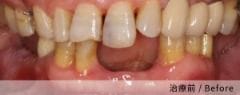

實際案例分享

案例二